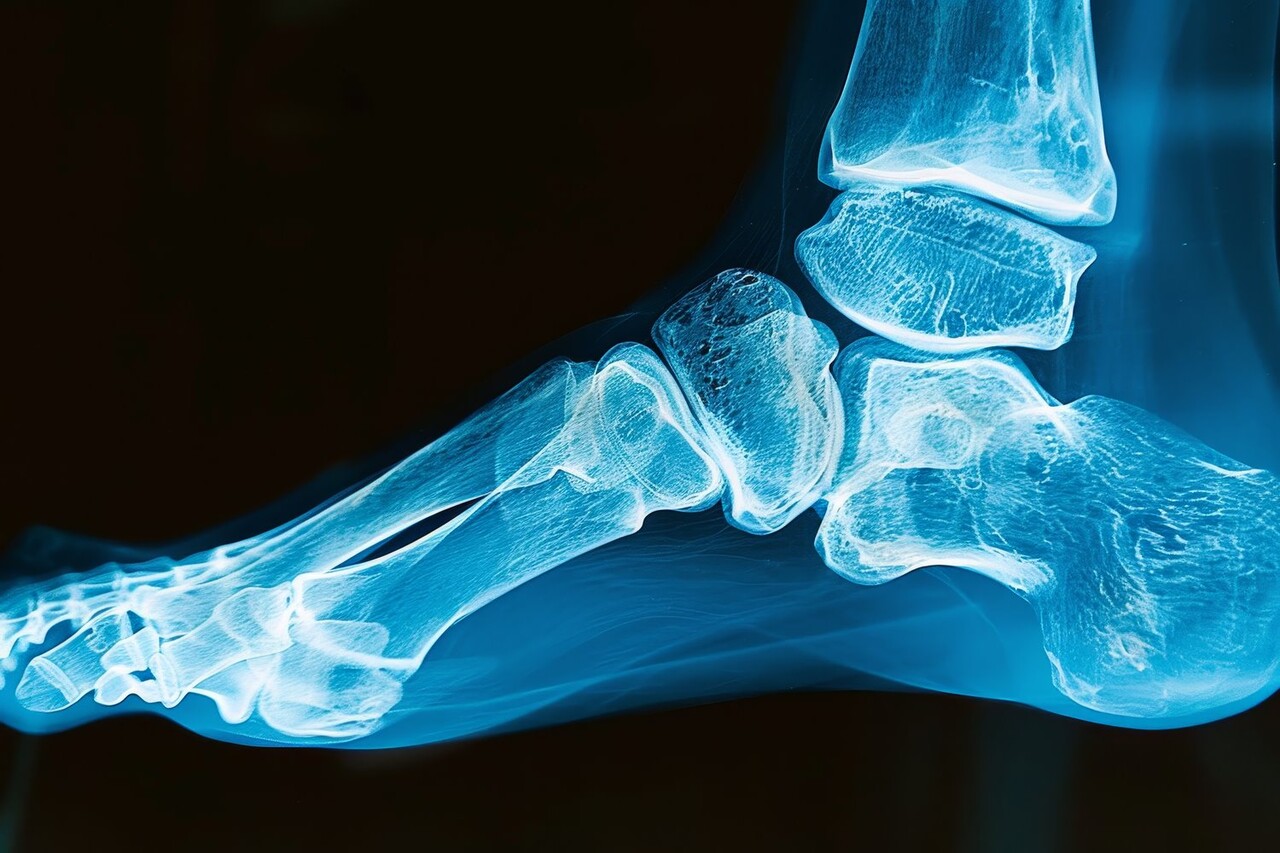

뼈와 뼈 사이를 연결하는 관절의 연골이 파괴되고 염증이 나타나는 질환을 '관절염(Arthritis)'이라 한다. 흔히 무릎이나 척추, 엉덩이를 생각하지만, 발목에서도 관절염이 발생한다.

발목관절염이란 정강이뼈와 발뼈를 잇는 발목관절에 염증이 생기는 질환이다. 주로 발목의 통증, 부기가 나타나고, 발목을 움직일 수 있는 운동범위가 제한된다. 유병률은 연구마다 차이가 있지만 전체 인구의 약 1%에서 3.4% 사이로 발생하는 것으로 알려져 있다.

'발목관절 유합술'은 발목관절의 경골과 거골을 하나의 나사로 고정하는 수술법을 말한다. 장점이라면 마모된 연골 부위를 모두 없애고 단단히 고정하기 때문에 통증을 크게 줄일 수 있다는 것이다. 반면, 단점은 관절의 가동범위가 줄어들고 향후 인접한 관절에도 관절염이 발생할 수 있다.

'발목관절 전치환술'은 발목관절 자체를 인공관절로 바꾸는 수술법이다. 관절의 가동범위는 상대적으로 보존된다는 장점이 있지만, 임플란트의 수명이 존재하기 때문에 추후 재수술이 필요할 수 있다는 것이 단점이다.